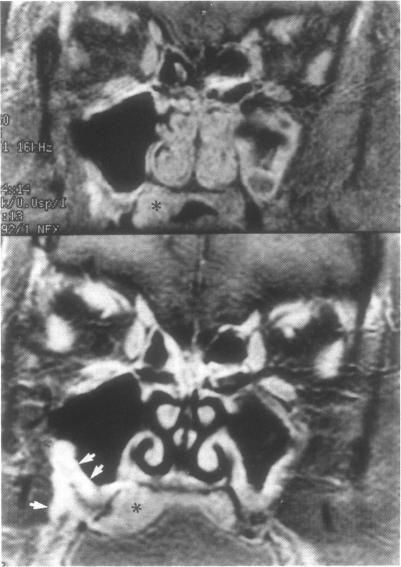

Adenoid cystic carcinoma of the hard or soft palate is a slow-growing, insidious disease with a tendency to spread via a perineural mechanism along the palatine branches of the maxillary division of the trigeminal nerve. Such spread may present first as a tumor in the pterygopalatine fossa or cavernous sinus. The purpose of this manuscript is to report three cases of palatal adenoid cystic carcinoma which presented as a mass in the cavernous sinus prior to discovery of the palate primary tumor. The imaging features of these cases are emphasized as is the need to search for a head and neck primary lesion when faced with a cavernous sinus mass.

硬腭或软腭的腺样囊性癌是一种生长缓慢、隐匿性疾病,有通过神经周围机制沿三叉神经上颌支的腭支扩散的倾向。这种扩散最初可能表现为翼腭窝或海绵窦内的肿瘤。本文的目的是报告三例腭腺样囊性癌病例,这些病例在发现腭部原发肿瘤之前,表现为海绵窦内的肿块。强调了这些病例的影像学特征,以及面对海绵窦肿块时寻找头颈部原发病变的必要性。